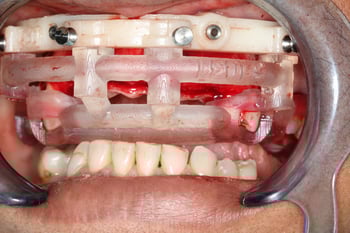

Definitive Mandibular Solution: Conus Overdenture

For the lower arch, we selected a Conus overdenture featuring titanium abutments milled to 5 degrees with precisely fitted gold copings. This friction-fit design provides excellent retention while allowing the patient to remove the prosthesis for hygiene.

The approach delivered an ideal balance of stability, cleansability, and long-term serviceability, making the implant overdenture both functional and patient-friendly.